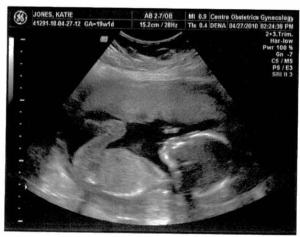

Here are a couple of ultrasound images of little McLain (Mamabea’s maiden name, and the little boy’s handle). He will go by the name McLain, but we still have to decide on his first name.

For the first time since Katie’s been pregnant the second time, she predicted a boy, in a note she sent me this morning. Her prediction was validated with an image at 2:15 p.m. as Sarah, Katie, and I looked at the screen on the wall during an ultrasound. When we checked in with Katie’s OB today, the fetus was 15.2 cm with a 143 bpm heart rate. We’re thrilled of course, although Katie and I agreed last week that we would be every bit as excited for Jackie to have a little sister.